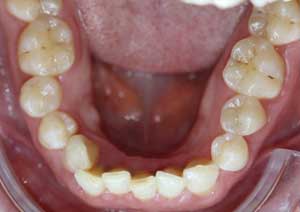

La supraclusion est définie comme le recouvrement excessif des incisives mandibulaires (inférieures) par les incisives maxillaires (supérieures).

Cliniquement, cela signifie qu’au sourire, le patient ne laisse pas apparaître les dents inférieures.

Il s’agit d’un problème de dimension verticale, fréquemment rencontré en pratique orthodontique quotidienne.

Avant